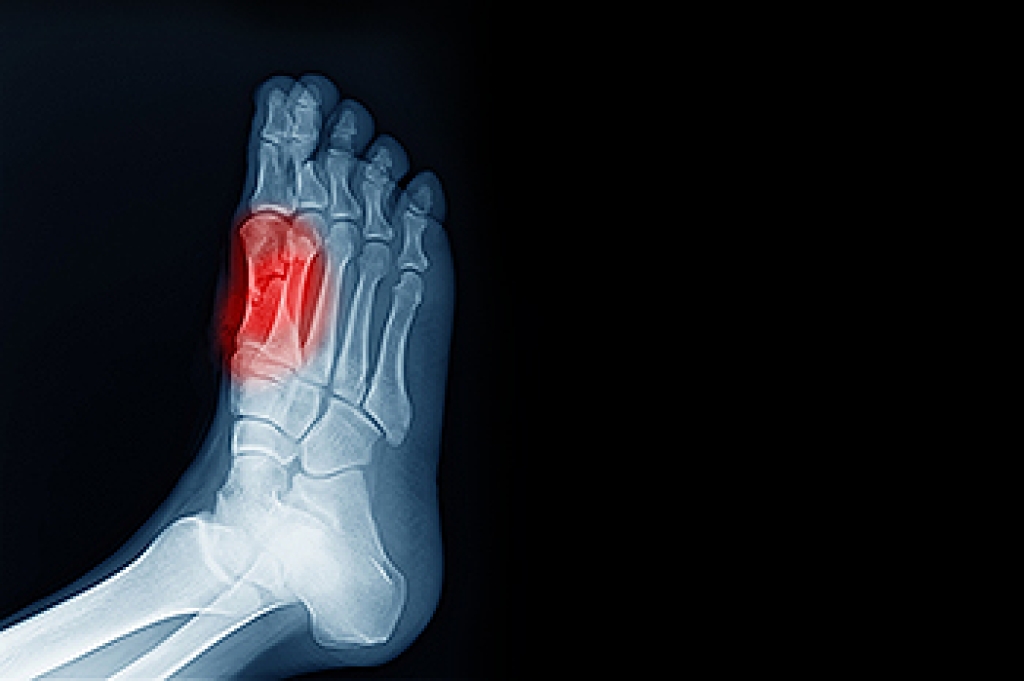

Sesamoiditis is a condition that affects the sesamoid bones, which are small, rounded bones located beneath the big toe joint. This ailment is a frequent contributor to metatarsalgia, a type of foot pain that occurs in the ball of the foot. Symptoms of sesamoiditis typically include pain and swelling surrounding the big toe joint, especially when engaging in activities that place pressure on the forefoot, such as dancing or jogging. Those who are at higher risk include dancers, who often perform on the balls of their feet, and joggers, who may experience repeated stress in this area. Wearing proper footwear, rest, and medical evaluation from a podiatrist is essential for managing this condition and alleviating discomfort. If you have pain in this part of your foot, it is suggested that you schedule an appointment with a podiatrist who can offer you effective treatment solutions.

Sesamoiditis is a condition of the foot that affects the ball of the foot. It is more common in younger people than it is in older people. It can also occur with people who have begun a new exercise program, since their bodies are adjusting to the new physical regimen. Pain may also be caused by the inflammation of tendons surrounding the bones. It is important to seek treatment in its early stages because if you ignore the pain, this condition can lead to more serious problems such as severe irritation and bone fractures.